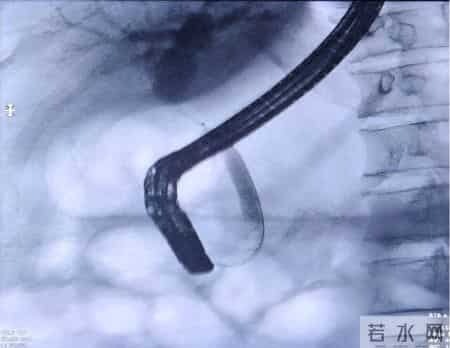

专家团队达成共识:病变部位不能排除为恶性肿瘤所致,应立即为患者实施胆道子镜检查+组织活检,明确病变性质后再制定个体化治疗方案,如果为良性病变,内镜治疗即可。通过子镜观察到患者胆总管上段存在一处长约1cm的狭窄并增厚胆管壁,并在病变部位精准钳取3块组织样本。果然,病理报告提示腺癌,这一结果证实了专家团队的初步判断。拿到诊断报告后,患者及家属陷入了悲痛之中,但罗宏武主任团队及时给予了心理疏导与信心鼓励,专家们的专业解读与暖心安慰,让患者及家属重新燃起了希望。